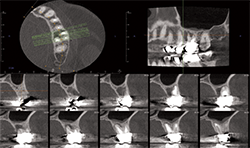

Case 1: 12-year-old boy with delayed eruption of the mandibular left second molar

The panoramic radiograph (Fig. 1) shows a well-defined, corticated, radiolucent area mesial to the mandibular left second molar. The inferior alveolar nerve canal is displaced inferiorly.

CBCT images of the same patient (Figs. 2A, 2B, 2C) reveal the lesion extends mesial to the third molar follicle, displacing the thinning buccal cortex. The lesion arises from the cementoenamel junction (CEJ) of the second molar. The inferior alveolar nerve canal is intact. The lesion was treated by surgical removal and submitted for histological examination. The histopathologic diagnosis was a dentigerous cyst.